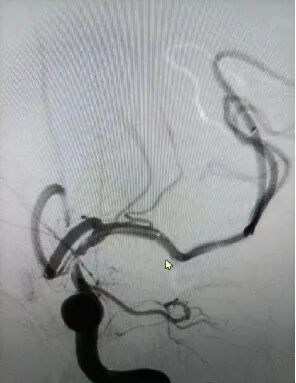

导引导管到位,微导丝携微导管通过病变,造影示后交通段重度狭窄,左侧大脑中下干闭塞。

导丝怎么扩【载药时代 球扩天下】NOVA DES®颅内药物洗脱支架在颈内动脉颅内段重度狭窄的应用两例!滕州市中心医院&山西医科大学第二医院_https://www.jmylbn.com_新闻资讯_第5张

微导丝进入下干,微导管进行机械碎栓。

导丝怎么扩【载药时代 球扩天下】NOVA DES®颅内药物洗脱支架在颈内动脉颅内段重度狭窄的应用两例!滕州市中心医院&山西医科大学第二医院_https://www.jmylbn.com_新闻资讯_第6张

◆ 狭窄血管情况

远端正常血管直径(mm):2.2mm

狭窄处最小直径(mm):次全闭塞

病变长度(mm):0.6mm

狭窄度(%):大于95%

下干顺利再通,300cm交换导丝交换下微导管,赛诺神畅内药物洗脱支架NOVA DES®进入颅内血管。

导丝怎么扩【载药时代 球扩天下】NOVA DES®颅内药物洗脱支架在颈内动脉颅内段重度狭窄的应用两例!滕州市中心医院&山西医科大学第二医院_https://www.jmylbn.com_新闻资讯_第7张

赛诺神畅内药物洗脱支架NOVA DES®通过闭塞段。

导丝怎么扩【载药时代 球扩天下】NOVA DES®颅内药物洗脱支架在颈内动脉颅内段重度狭窄的应用两例!滕州市中心医院&山西医科大学第二医院_https://www.jmylbn.com_新闻资讯_第8张